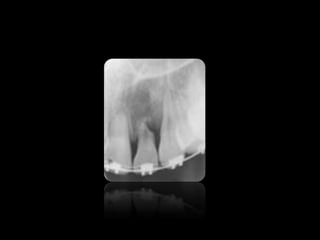

6.

CARIES